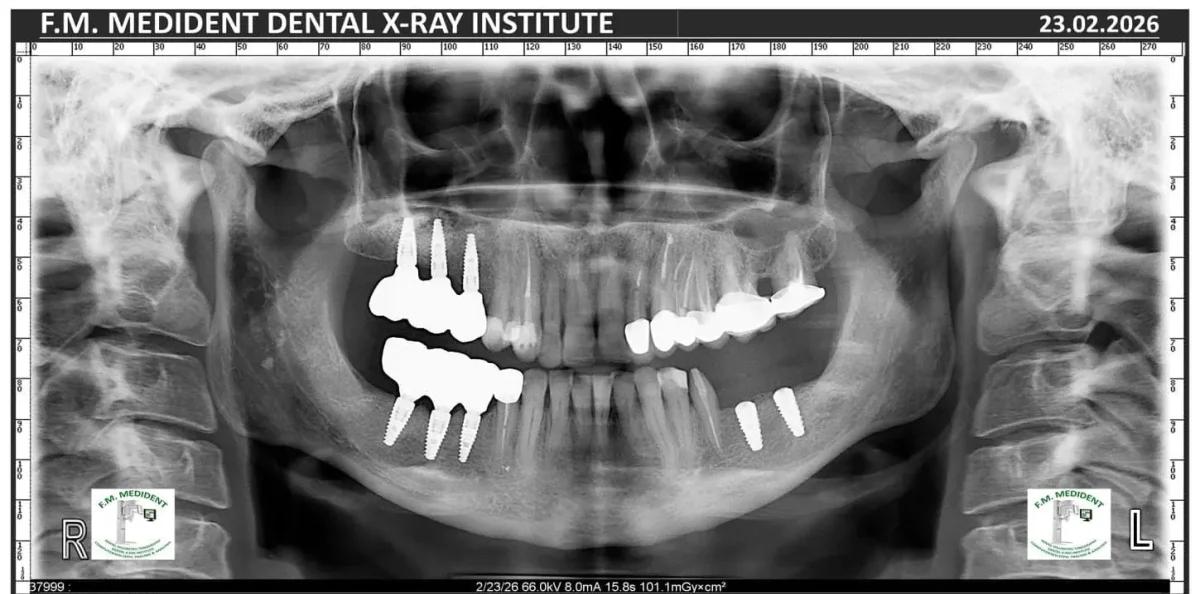

Cazuri reale înainte și după, din tratamente realizate în clinică.

Înainte

DupăExemple reale din cazuri tratate în clinică.